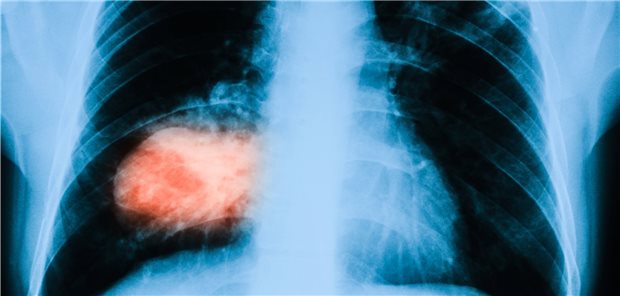

Forscher haben geprüft, ob bei Patienten mit inoperablem Lungenkrebs der Einsatz der 18F-fluorodeoxyglucose-PET zur Reduktion des Zielvolumens bei der Bestrahlungsplanung Vorteile bringt.